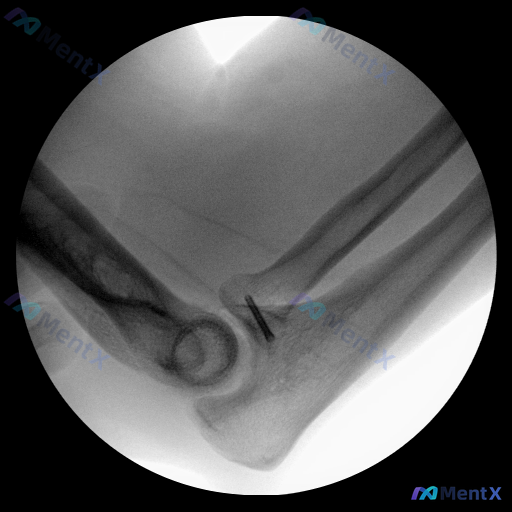

整理到一份肘关节的影像资料,先不放太多背景,仅看这张X光(侧/斜位): 核心影像表现: 1. 肱骨远端、尺骨近端、桡骨头的骨皮质轮廓大致清晰,关节对位尚好 2. 关键异常:在尺骨近端与肱骨远端关节间隙的前方,可见一枚线状高密度金属阴影,横穿部分关节间隙或邻近骨结构 3. 金属影附近的尺骨冠突区域,因...